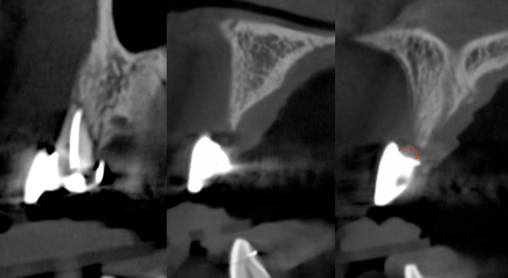

The patient had a congenitally missing upper right lateral incisor. Orthodontic treatment was performed to create the necessary space for a dental implant. Unfortunately, the implant failed, and so did several subsequent attempts to bone graft. These failures resulted in a visible smile deformity, that got worse after each failed procedure.

After the 3rd bone graft failed, the patient sought second opinions. She was a college sophomore at the time. Using a combination of interdisciplinary therapies, including S.M.A.R.T. minimally invasive bone grafting, Dr. Ernesto Lee was able to tridimensionally reconstruct this severe defect and place implants to restore the patient’s smile. The S.M.A.R.T. bone graft was also extended to treat adjacent teeth with thin/dehisced bone.